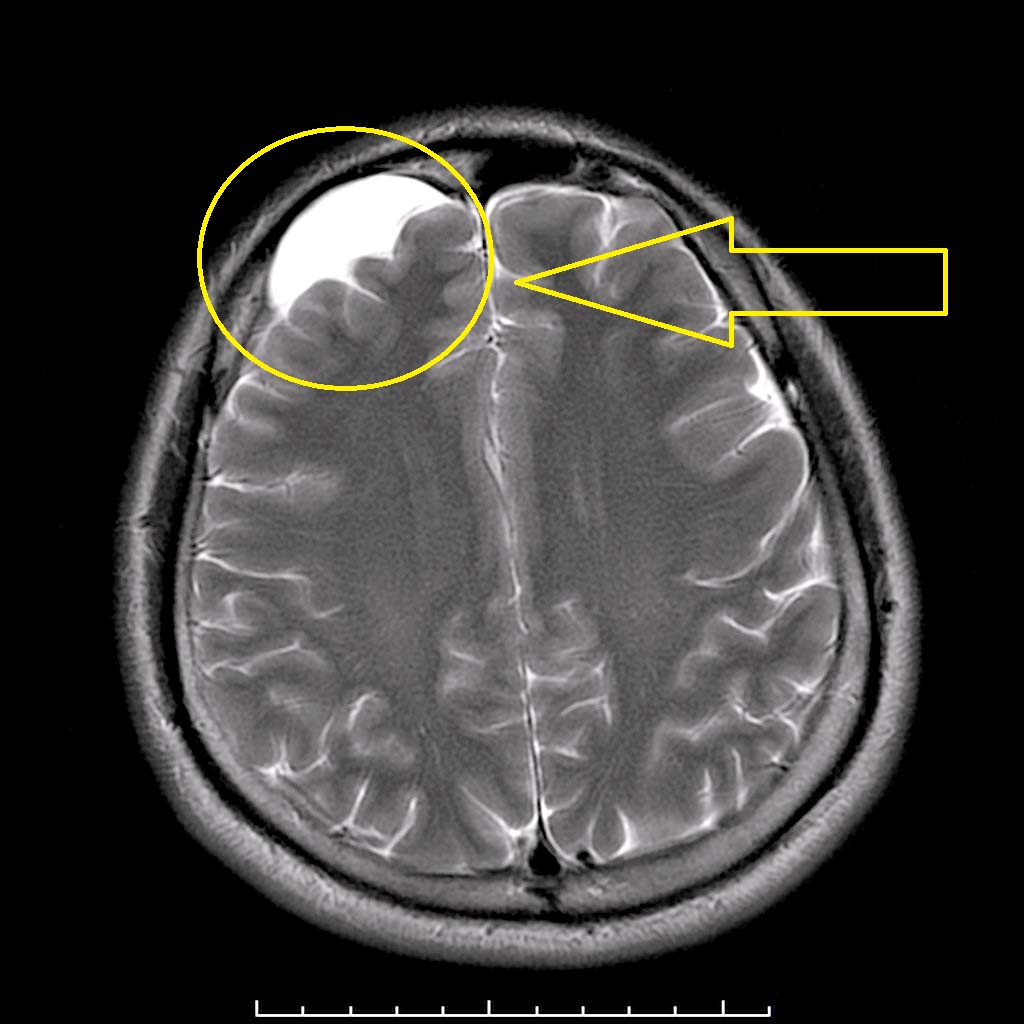

Основной метод диагностики, который позволяет получить всю необходимую информацию о новообразовании – МРТ. При небольшом размере, отсутствии жалоб со стороны пациента можно не принимать никаких мер.

Обязательным является постоянное отслеживание динамики состояния – при кистозном расширении может понадобиться хирургическое вмешательство.